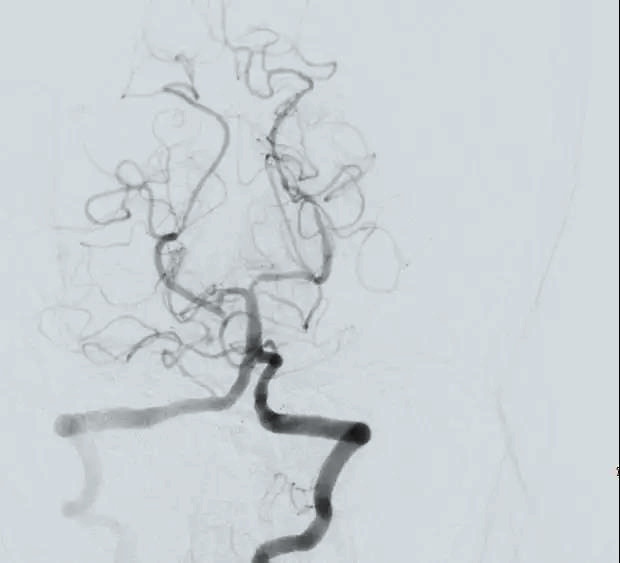

在神經(jīng)外科戴偉民主任的帶領(lǐng)下,李運(yùn)平、劉榮財(cái)醫(yī)生默契配合,團(tuán)隊(duì)協(xié)作為搶救生命爭(zhēng)分奪秒?!叭榧皠?dòng)脈置鞘,基底動(dòng)脈起始部完全閉塞。”腦血管造影再次印證葉女士危在旦夕?!霸偻硪环昼姡蠊豢霸O(shè)想!” DSA導(dǎo)管室,一場(chǎng)與時(shí)間賽跑的生命爭(zhēng)奪戰(zhàn)正在進(jìn)行。定點(diǎn)、介入,從放置取栓裝置到送達(dá)栓塞部位,每一個(gè)動(dòng)作都“重若千鈞”,終于在3毫米的動(dòng)脈導(dǎo)管內(nèi)完整取出5X3毫米的血栓,復(fù)查造影,顯示基底動(dòng)脈血流恢復(fù),取栓成功。而此時(shí),距離葉女士抵達(dá)DSA導(dǎo)管室,僅僅過去了20分鐘。

取栓前

取栓后